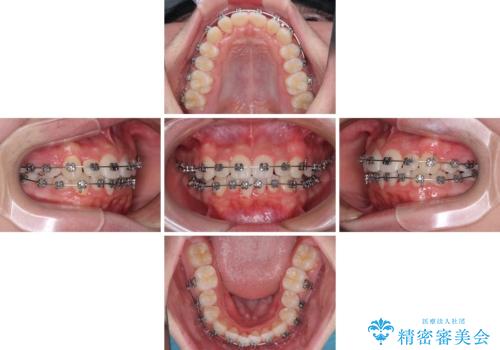

- 矯正装置

- メタルブラケット

- 治療期間

- 11ヶ月

- 治療回数

- 10-30回